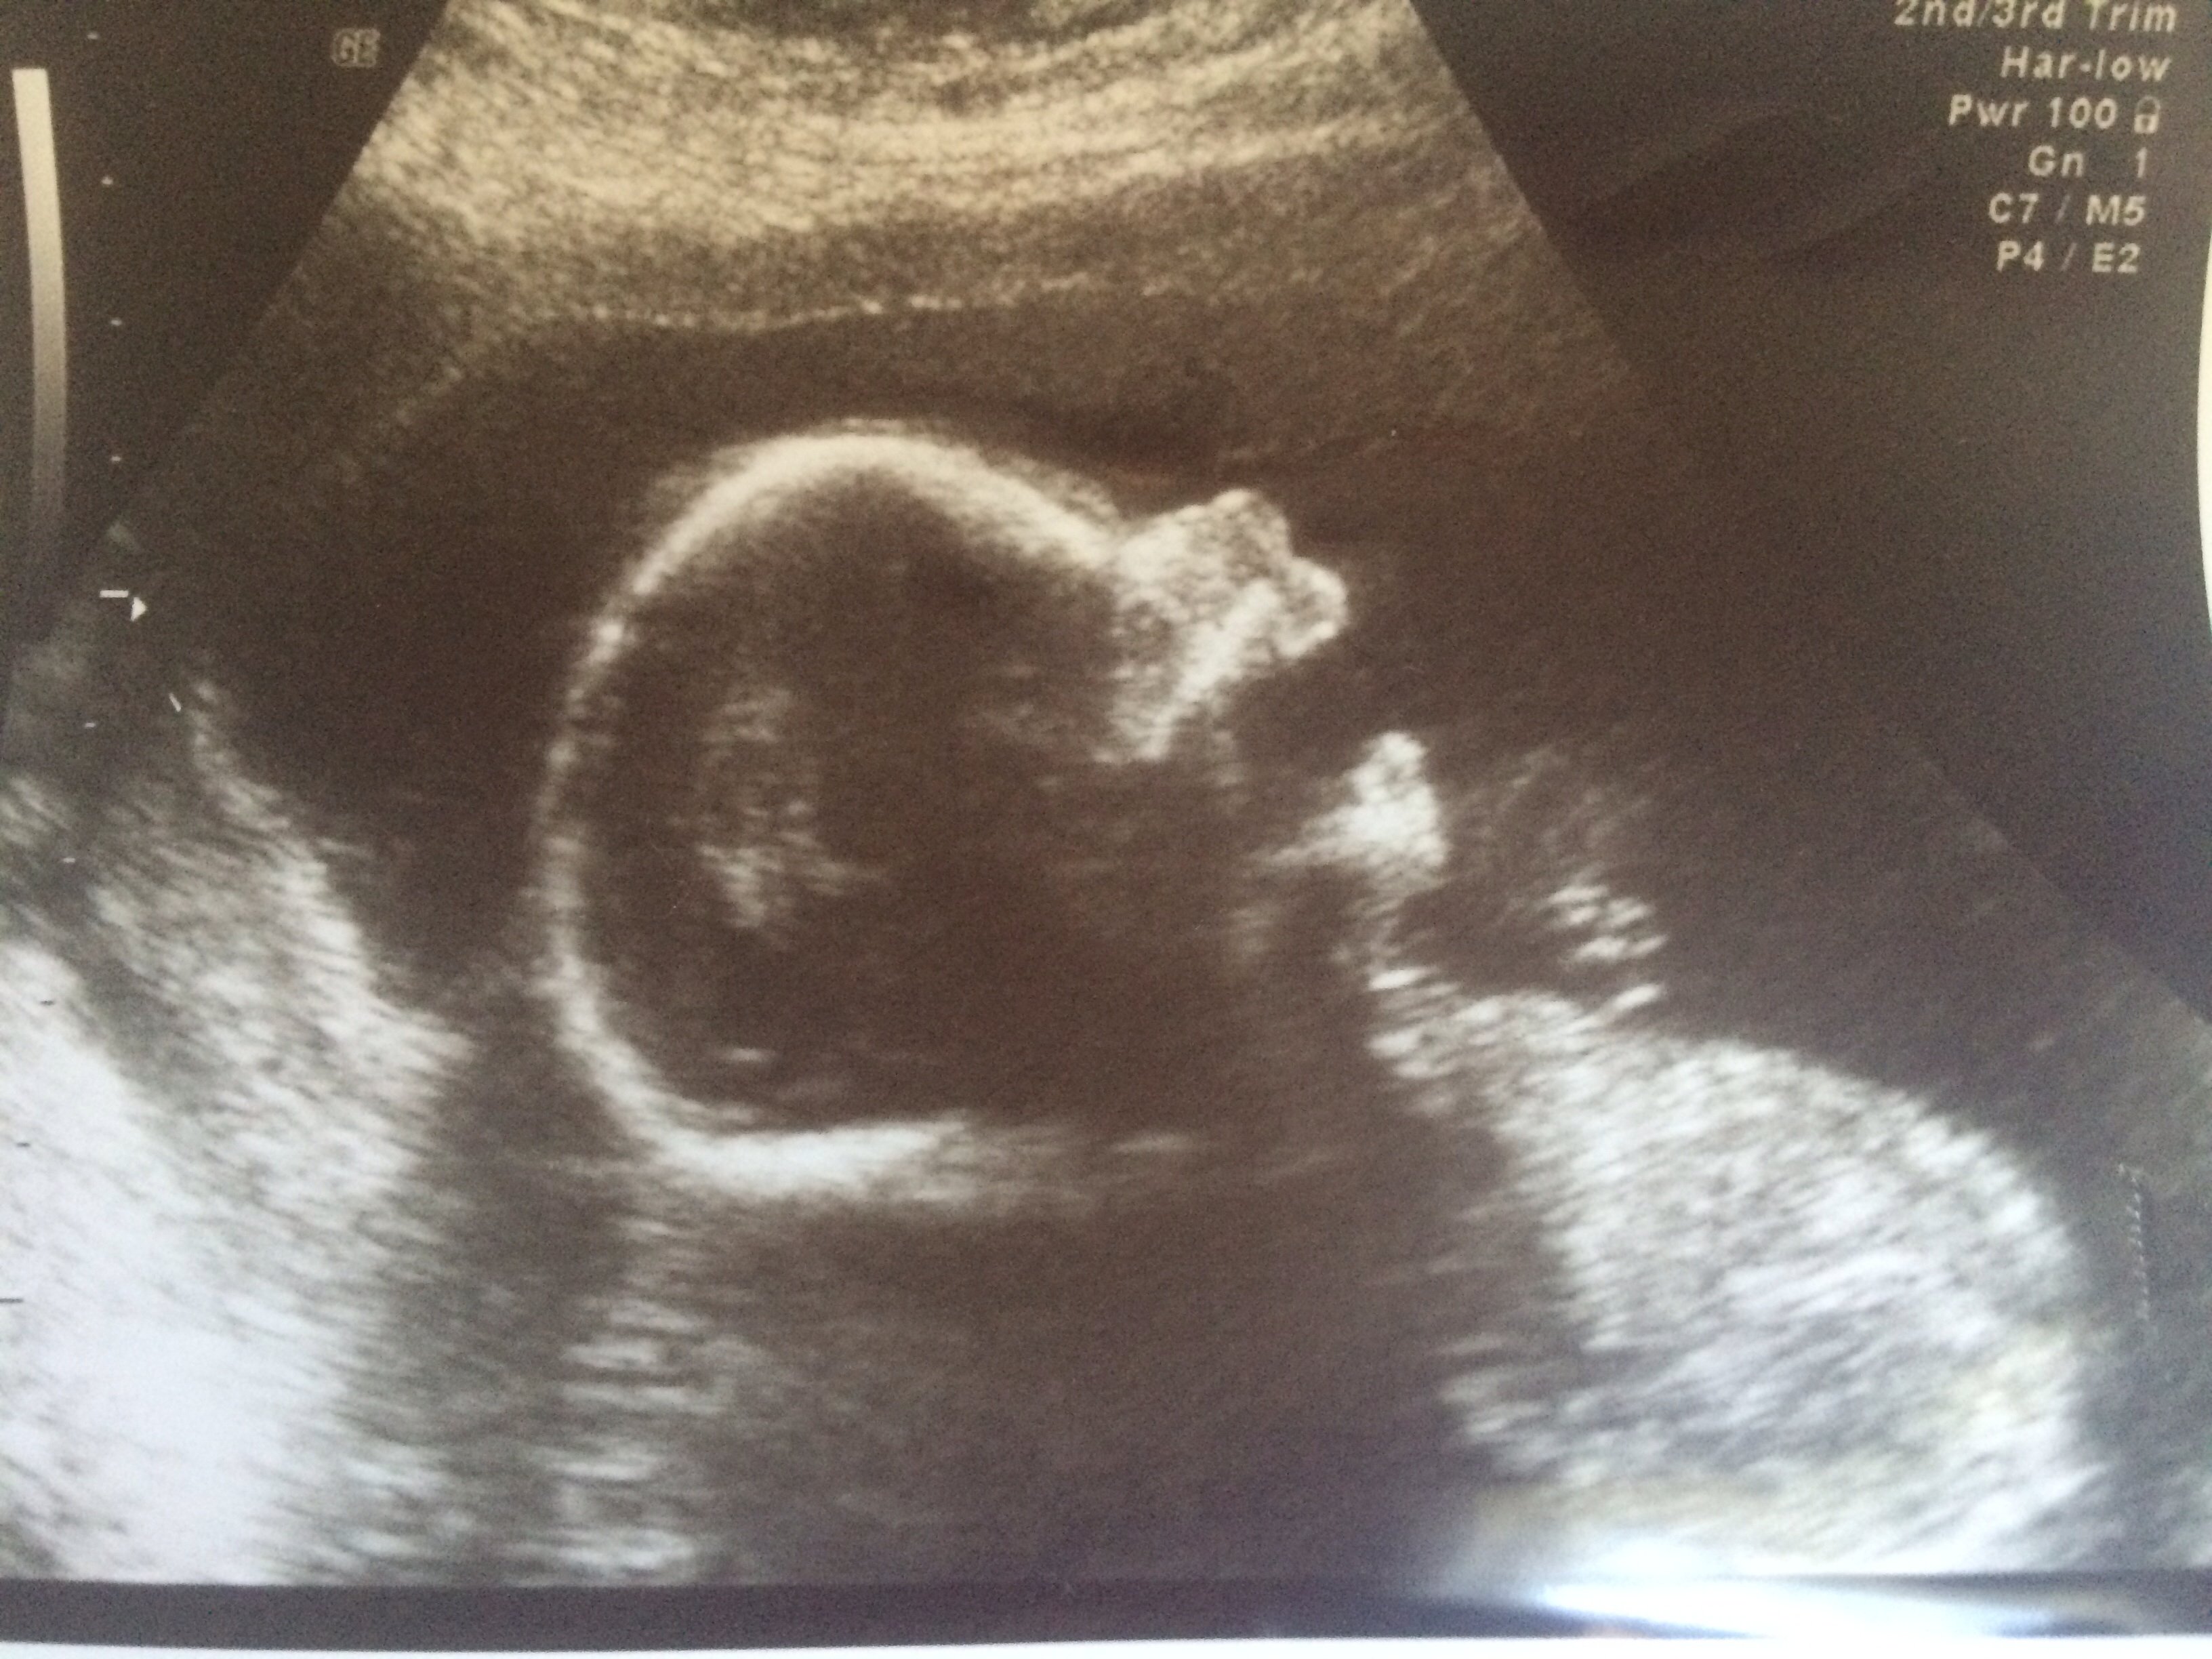

We found out we're having a girl...and we got a picture of her yawning.

So I never got to post: We're having a girl!!!

Super excited.